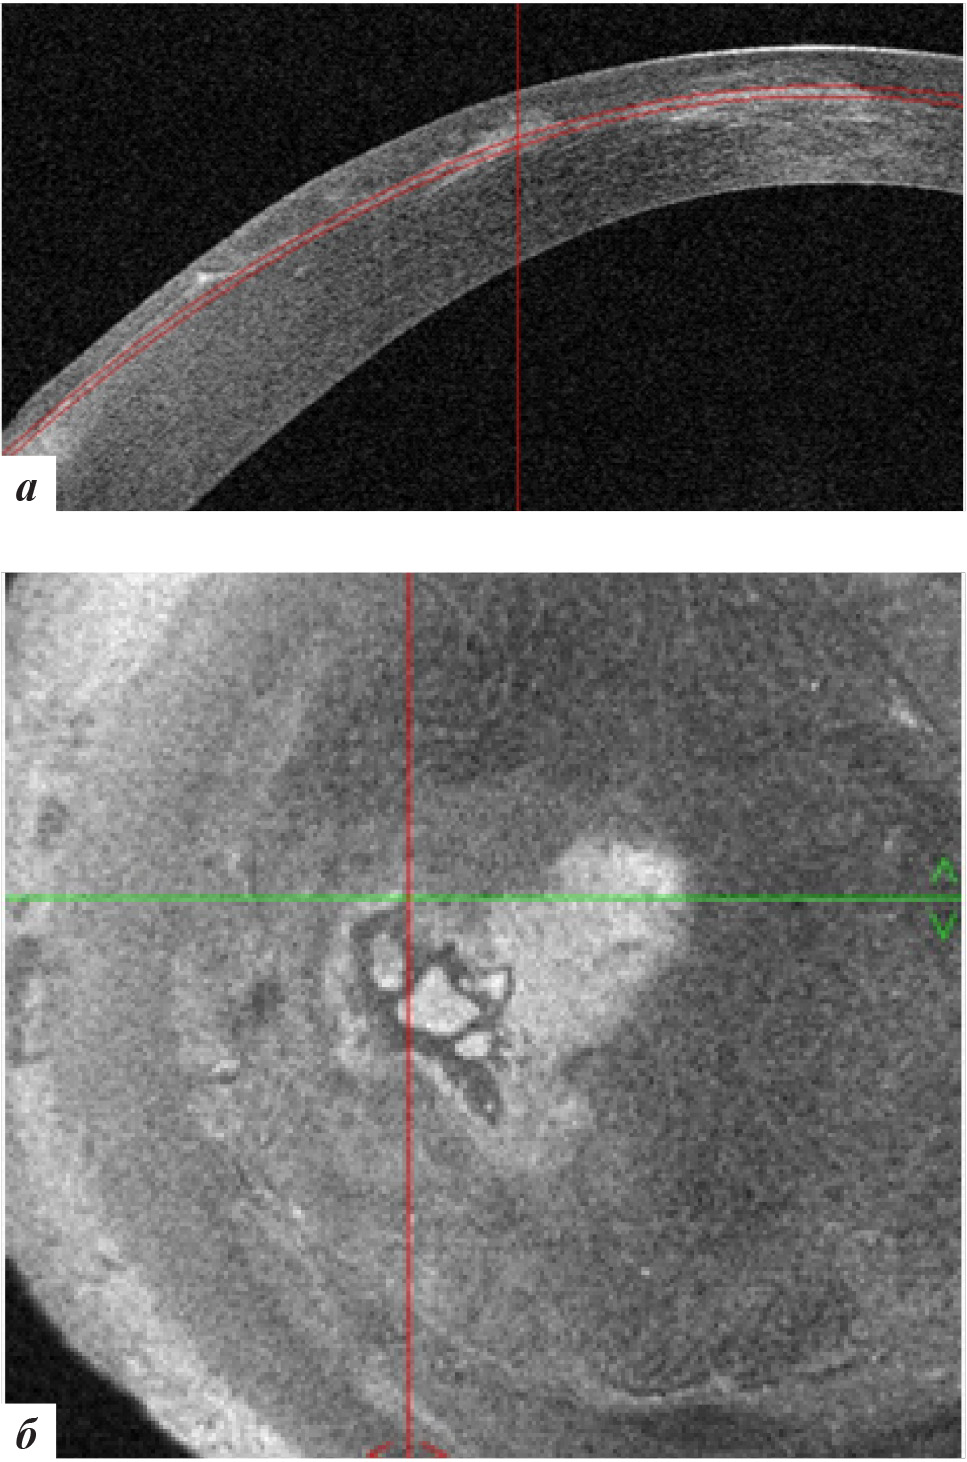

Рис. 2. Данные ОКТ роговицы правого глаза: а – горизонтальная проекция; б – фронтальная проекция

Рис. 4. Данные ОКТ роговицы левого глаза: а – горизонтальная проекция, б – фронтальная проекция

Рис. 7. Данные ОКТ роговицы левого глаза через 3 месяца после лечения: а – горизонтальная проекция, б – фронтальная проекция

Рис. 9. Данные ОКТ роговицы левого глаза через 9 месяцев после лечения: а – горизонтальная проекция, б – фронтальная проекция

Рис. 11. Данные ОКТ роговицы левого глаза через 18 месяцев после лечения: а – горизонтальная проекция, б – фронтальная проекция